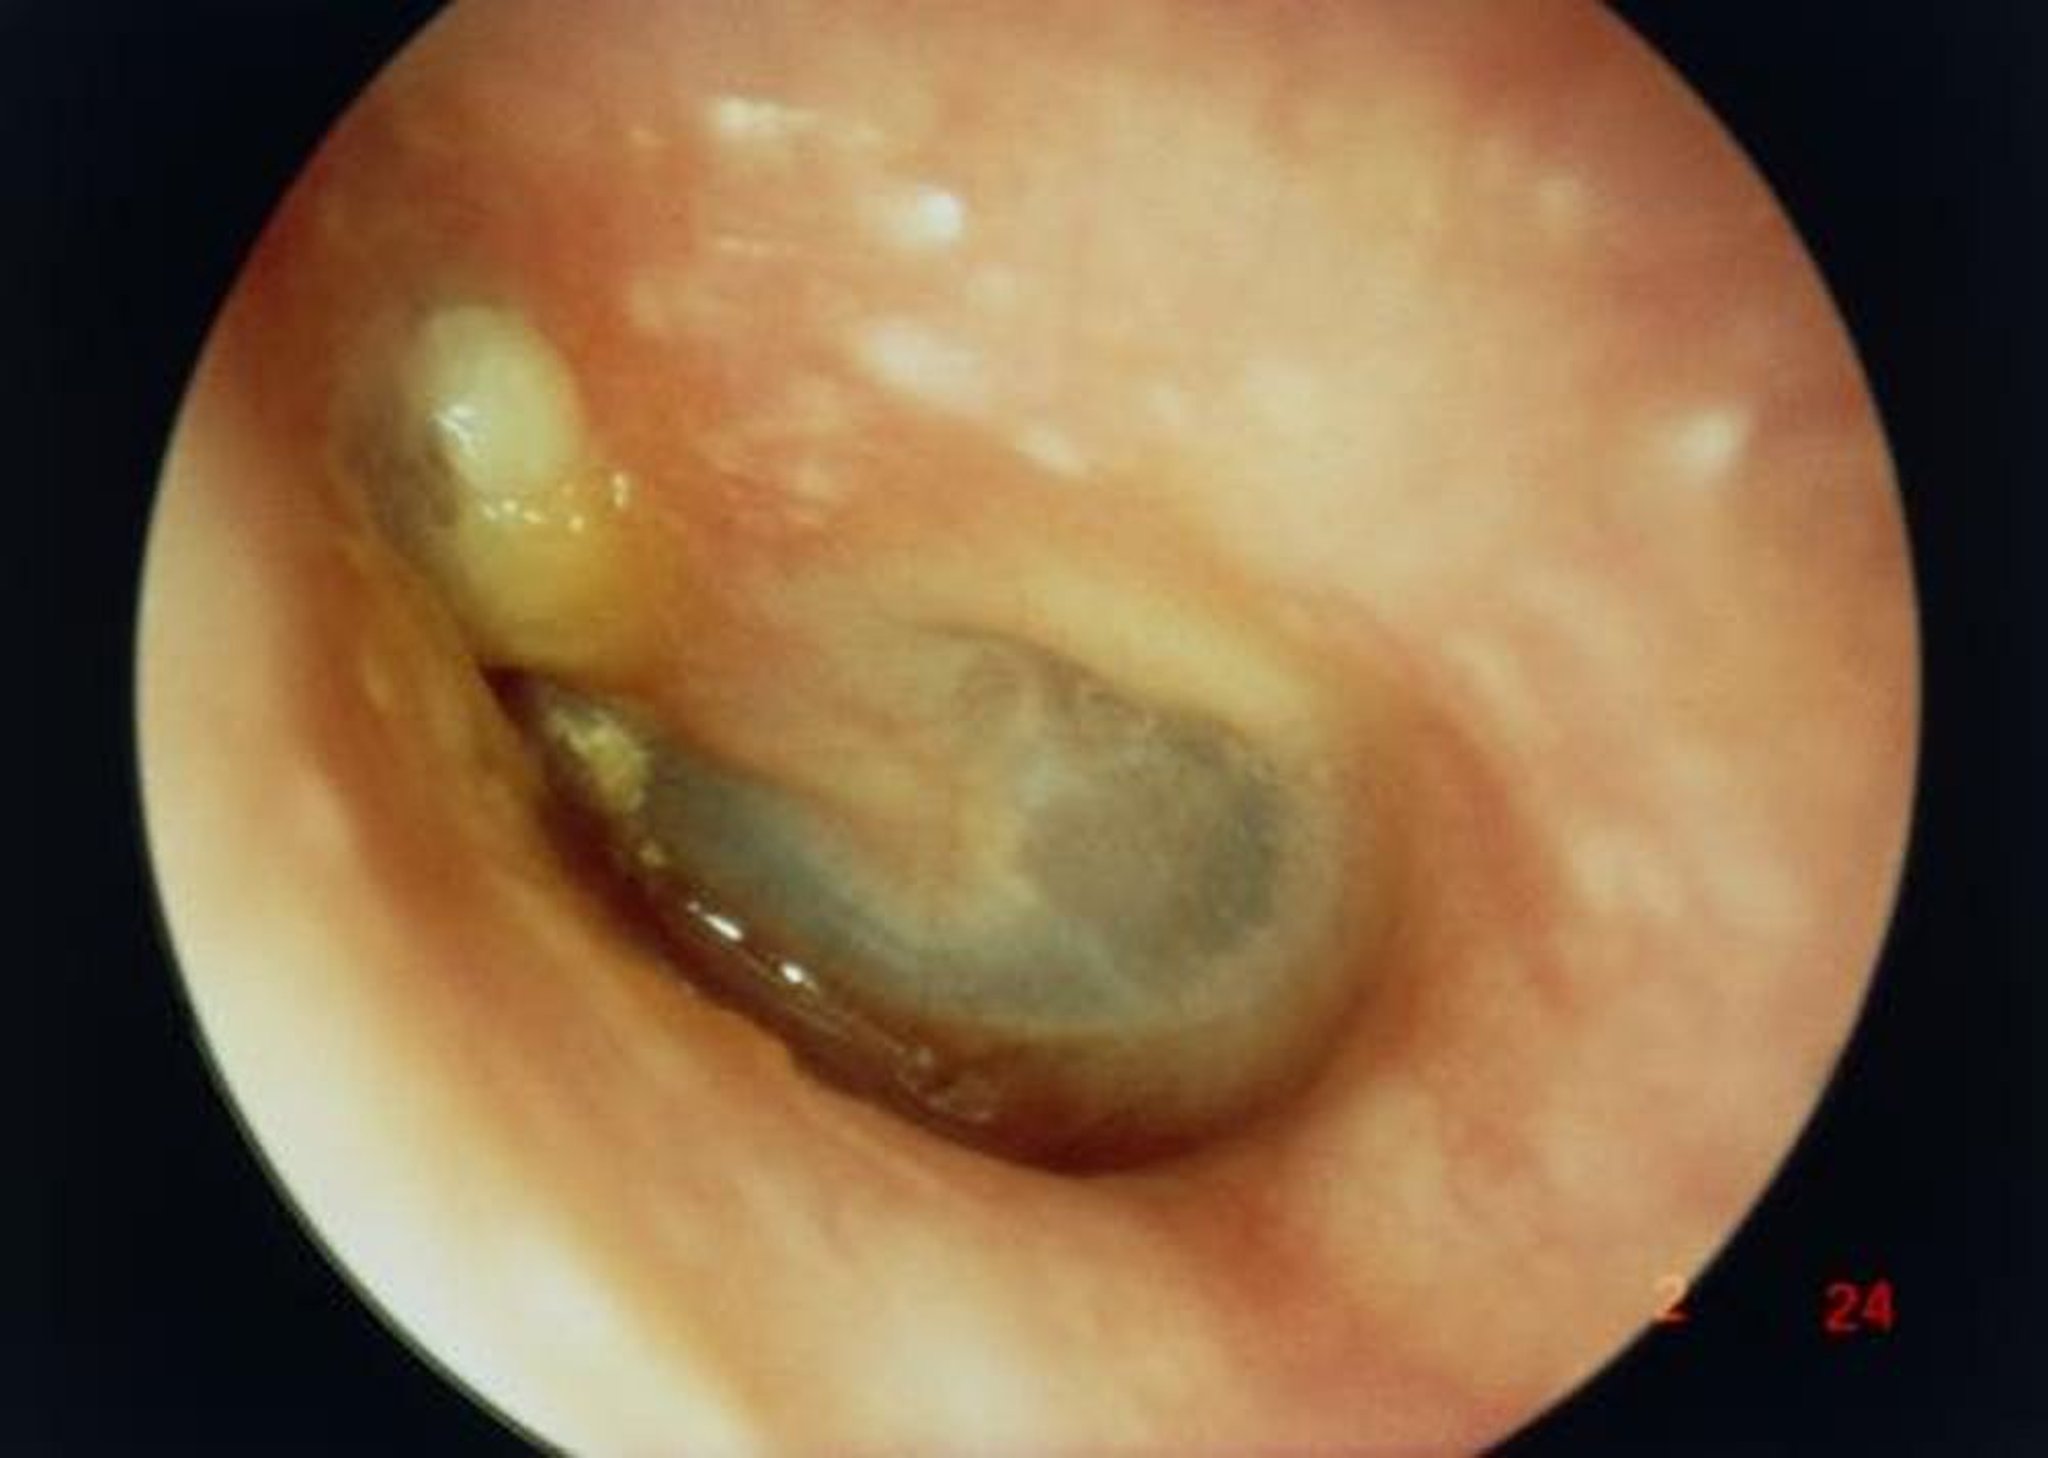

Dans cette image, la vue le long du conduit auditif externe montre un grand cholestéatome (masse blanche à gauche au-dessus du processus court du marteau) entraînant une perforation du tympan.

PROFESSOR TONY WRIGHT, INSTITUTE OF LARYNGOLOGY & OTOLOGY/SCIENCE PHOTO LIBRARY